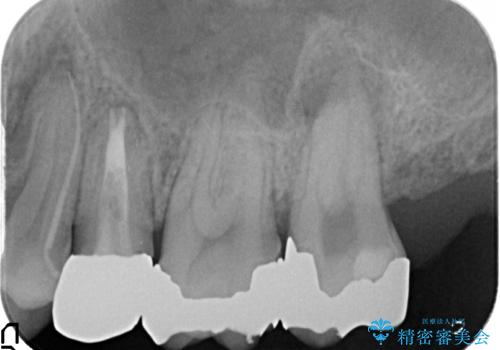

診査の結果、左上4番目の歯の神経が死んでおり、根尖に膿が溜まっていることが原因とわかりました。

そのため左上4番目の歯は根管治療を行い、歯茎の膿の出口の消失を確認後、オールセラミッククラウンによる補綴を行いました。